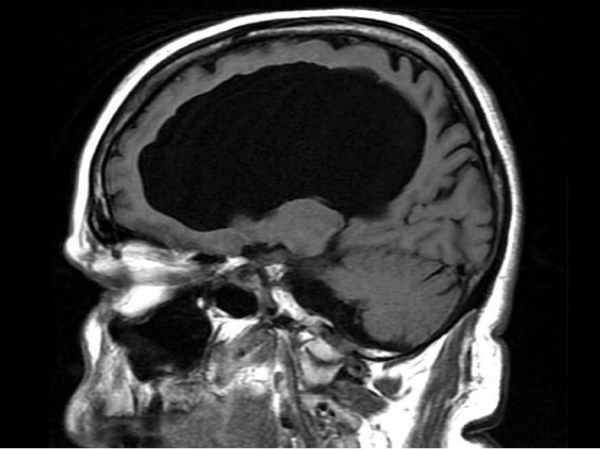

ಮೆದುಳು ಇಲ್ಲದೇ ಸಾಮಾನ್ಯರಂತೆ ಬದುಕುತ್ತಿರುವ ವ್ಯಕ್ತಿ

ಆ ಚಾಲೆಂಜ್ ಎನಂದ್ರೆ ಫ್ರಾನ್ಸ್ನ ವ್ಯಕ್ತಿಗೆ ಶೇಕಡ 90 ರಷ್ಟು ಮೆದುಳು ಇಲ್ವೇ ಇಲ್ಲ. ಆದರೂ ಸಹ ಈತ ಎಲ್ಲರಂತೆ ಜೀವನ ನಡೆಸುತ್ತಿದ್ದಾನೆ ಮತ್ತು ಹೆಂಡತಿ, ಮಕ್ಕಳೊಂದಿಗೆ ಸುಖವಾಗಿದ್ದಾನೆ. ಅಲ್ಲದೇ ಈತ ಸರ್ಕಾರಿ ನೌಕರಿಯಲ್ಲಿದ್ದಾನೆ. ಅದ್ ಹೇಗ್ ಸಾಧ್ಯ ಅಂತ ಪ್ರಶ್ನೆ ಕೇಳುವವರೆಲ್ಲಾ ಈ ಬಗ್ಗೆ ವಿಶೇಷ ಮಾಹಿತಿಯನ್ನು ಲೇಖನದ ಸ್ಲೈಡರ್ ಕ್ಲಿಕ್ಕಿಸಿ ಓದಿರಿ.

ಫ್ರಾಂನ್ಸ್ ವ್ಯಕ್ತಿಗೆ ಶೇಕಡ 90 ರಷ್ಟು ಮೆದುಳು ಇಲ್ಲದಿರುವ ಬಗೆಗಿನ ಅಧ್ಯಯನ ವರದಿ ಬ್ರಿಟನ್ನ ಮೆಡಿಕಲ್ ನಿಯತಕಾಲಿಕೆ 'ದ ಲ್ಯಾನ್ಸೆಟ್'ನಲ್ಲಿ ಪ್ರಕಟವಾಗಿದೆ.

ಬ್ರಿಟನ್ನ ಮೆಡಿಕಲ್ ನಿಯತಕಾಲಿಕೆ ' ದ ಲ್ಯಾನ್ಸೆಟ್' ಪ್ರಕಾರ ''44 ವರ್ಷದ ಫ್ರೆಂಚ್ ವ್ಯಕ್ತಿಯು ತನ್ನ ಎಡಗಾಲಿನ ದೌರ್ಬಲ್ಯದ ಬಗ್ಗೆ ತೋರಿಸಿಕೊಳ್ಳಲು ಡಾಕ್ಟರ್ ಬಳಿ ಹೋಗಿದ್ದ. ವೈದ್ಯರು ಕಾಲಿನ ದೌರ್ಬಲ್ಯಕ್ಕೆ ಮೂಳೆಗಳ ಯಾವುದೇ ಕಾರಣವನ್ನು ಪತ್ತೆ ಮಾಡಲು ಸಾಧ್ಯವಾಗದಿದ್ದಾಗ, ಮೆದುಳನ್ನು ಹತ್ತಿರದಿಂದ ನೋಡಲು ಮ್ಯಾಗ್ನೆಟಿಕ್ ರೆಸೋನೆನ್ಸ್ ಇಮೇಜಿಂಗ್ ತೆಗೆದರು. ಮೆದುಳಿನ ತುಂಬಾ ಹತ್ತಿರದ ಚಿತ್ರ ನೋಡಿದ ವೈದ್ಯರು ಸಂಪೂರ್ಣ ಮೆದುಳು ಇಲ್ಲದಿರುವುದನ್ನು ನೋಡಿ ಶಾಕ್ ಆದರಂತೆ.

ಮೆಡಿಕಲ್ ಇತಿಹಾಸದಲ್ಲಿ ಇದುವರೆಗೂ ನೋಡದ ವೈದ್ಯರುಗಳಾದ 'ಲಿಯೋನೆಲ್ ಫ್ಯೂಲ್ಲೆಟ್, ಹೆನ್ರಿ ಡುಫೊರ್ ಮತ್ತು ಜೀನ್ ಪೆಲ್ಲೆಟಿಯರ್'ರವರು ಆತ ಜಲಮಸ್ತಿಷ್ಕ ರೋಗದಿಂದ ಜನಿಸಿರುವುದನ್ನು ಪತ್ತೆಹಚ್ಚಿದ್ದಾರೆ.

ಫ್ರೆಂಚ್ ವ್ಯಕ್ತಿಯು ಹುಟ್ಟುತ್ತಾ ಜಲಮಸ್ತಿಷ್ಕ ರೋಗದಿಂದ ಜನಿಸಿದ್ದು, ಆತನ ಮೆದುಳನ್ನು ಷಂಟ್ ದ್ರವವು ನಶಿಸಿರುವಿಕೆಯನ್ನು ಪತ್ತೆ ಮಾಡಿದ್ದಾರೆ.

ವ್ಯಕ್ತಿಯು 14 ವರ್ಷದವನಾಗಿದ್ದಾಗ ಆತನ ಮೆದುಳನ್ನು ನಶಿಸುತ್ತಿದ್ದ ಷಂಟ್ ದ್ರವವನ್ನು ವೈದ್ಯರು ತೆಗೆದಿರುವ ಬಗ್ಗೆ ತಿಳಿಯಲಾಗಿದೆ.

ವ್ಯಕ್ತಿಯಲ್ಲಿ ಷಂಟ್ ದ್ರವವು ಹೀಗೆ ಹರಿಯುತ್ತಿದ್ದರೆ ಇರುವ ಶೇಕಡ 10 ರಷ್ಟು ಮೆದುಳನ್ನು ನಶಿಸಿಬಿಡುತ್ತದೆ. ಆದರೆ ವ್ಯಕ್ತಿ ಸಂಪೂರ್ಣ ಚಟುವಟಿಕೆಯುಳ್ಳವನಾಗಿದ್ದು ವೈದ್ಯರು ಕುತೂಹಲ ವ್ಯಕ್ತಪಡಿಸಿದ್ದಾರೆ.

ವ್ಯಕ್ತಿಯು ಸಂಪೂರ್ಣ ಮೆದುಳಿನ ಹಿಪೊಕ್ಯಾಂಪಸ್ ಇಲ್ಲದೇ ಎಲ್ಲಾ ಮಾಹಿತಿಗಳನ್ನು ನೆನಪು ಮಾಡಿಕೊಳ್ಳುತ್ತಾನೆ. ಸಂಪೂರ್ಣ ಗಾತ್ರದ ಹಿಪೊಕ್ಯಾಂಪಸ್ ಇಲ್ಲದೇ ದೇಹದ ಉಷ್ಣತೆಯನ್ನು ನಿಯಂತ್ರಿಸುತ್ತಾರೆ. ಸಾಮಾನ್ಯ ಹಿಮ್ಮೆದುಳು ಇಲ್ಲದೇ ನಡೆದಾಡುತ್ತಾರೆ. ಇದು ವೈದ್ಯಲೋಕವನ್ನು ತಲ್ಲಣಗೊಳಿಸುವ ಮಾಹಿತಿಯಾಗಿದ್ದು ಹಲವು ಪ್ರಶ್ನೆಗಳನ್ನು ಹುಟ್ಟಿಹಾಕಿದೆ.

'ವ್ಯಕ್ತಿಯನ್ನು ವೈದ್ಯಕೀಯ ಪರೀಕ್ಷೆಗೆ ಒಳಪಡಿಸಿದಾಗ ಆತನಲ್ಲಿ 'ಬುದ್ಧಿಮತ್ತೆಯ ಪ್ರಮಾಣ (Intelligence quotient)' ಶೇಕಡ 75 ಇದ್ದು, ಕನಿಷ್ಠ ಶೇಕಡ 100 ಕ್ಕೆ ಕಡಿಮೆ ಇದೆ. ಆದರೆ ಅತಿ ಕಡಿಮೆ ಇಲ್ಲ ಎಂದು ಹೇಳಲಾಗಿದೆ.